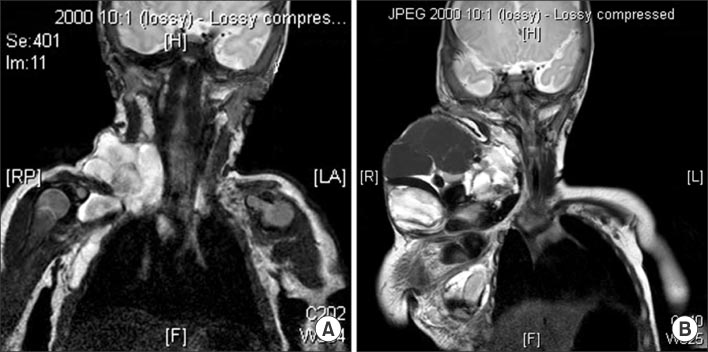

Fig. 4

(A) MRI shows macrocystic lymphatic malformations which are involving from right neck to axilla before OK-432 sclerotherapy (patient No. 9). (B) Intralesional hemorrhage happened one month after sclerotherapy.

Fig. 5 (A) Sagittal T2-weighted MRI shows cervical lymphangioma which are infiltrating tongue base (patient No. 11). (B) Decreased lymphatic malformation after surgery.